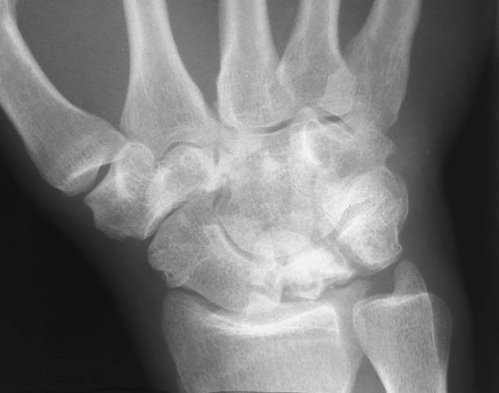

Lunatomalacia

Lunatomalacia. The lunate is denser and more deformed than the other bones. There is also osteoarthritis of the wrist.